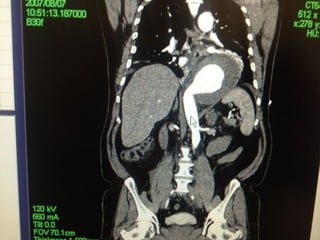

• Preoperative CT 1mm imaging to include pelvisPreoperative CT 1mm imaging to include pelvis